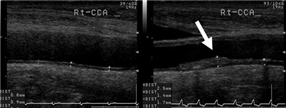

動脈硬化

この心筋梗塞や脳梗塞のほとんどは

動脈硬化が原因です。

心臓から体中に酸素や栄養素を運ぶのが動脈で、

生まれた瞬間から加齢とともに老化し、

弾力性を失い硬くなったり

動脈内の悪玉コレステロールや中性脂肪が

活性酸素と結びつき酸化することで

過酸化脂質となり

血管壁に付着し血管を詰まらせ、

血管が破れたりする状態を動脈硬化といいます。